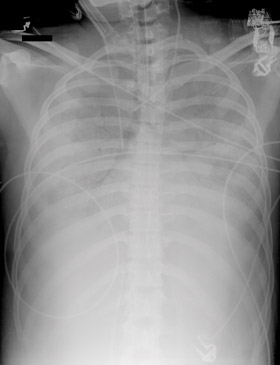

4 Examples of cannulation for venoarterial (VA) and venovenous (VV) extracorporeal membrane oxygenation (ECMO), and circuitry used for both

![]() |